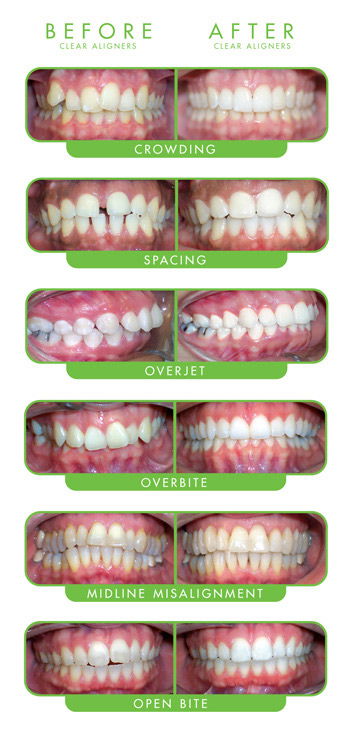

Aligners

Aligners are transparent custom made dental braces made of plastic material.They are made to fit each person’s mouth. These are the least visible orthodontic treatment available. The aligners cannot be seen in photographs or from a far.These braces are clear and blend in more with the natural colour of the teeth. The idea of getting braces is more acceptable because of Aligners. Conventional braces use metal / ceramic brackets connected by wires to achieve desired movement of teeth. These braces are metal based and are visible when you smile or talk making your look unaesthetic. Aligners are an extraordinary option for patients who would prefer not to wear conventional braces.